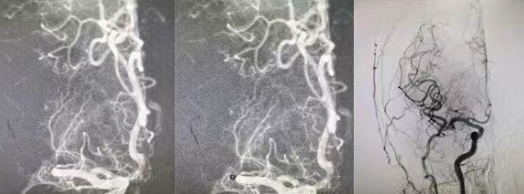

結(jié)合患者癥狀,團隊判斷其為大腦中動脈主干閉塞、大面積血栓,單純?nèi)芩y以徹底打通血管,當(dāng)即果斷制定溶栓后橋接血管內(nèi)拉栓的最優(yōu)救治方案。在溶栓起效的黃金窗口期,醫(yī)護人員迅速將患者轉(zhuǎn)入介入手術(shù)室,全力實施血管拉栓手術(shù)。術(shù)中,介入醫(yī)生精準(zhǔn)定位閉塞血管,憑借嫻熟的微創(chuàng)技術(shù),順利取出堵塞血栓,閉塞的大腦中動脈成功再通,腦部血流恢復(fù)通暢,僅用20分鐘便完成了從穿刺到取栓的全部操作。

從患者入院到溶栓完成,再到血管拉栓成功,整個救治過程高效連貫、環(huán)環(huán)相扣,刷新了醫(yī)院急性大面積腦血栓的急救速度。目前,患者生命體征平穩(wěn),左側(cè)肢體功能正逐步恢復(fù),已成功脫離生命危險,順利進(jìn)入術(shù)后康復(fù)階段。